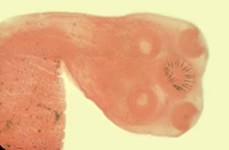

¿Cuál de los

siguientes corresponde al escólex de una Taenia solium?

Paciente

masculino de 9 meses de edad quien es llevado por la madre a la emergencia

porque ha notado que su hijo está “un poco cabezoncito” a comparación de sus

hermanos mayores a esa edad. Mencionan que viven como criadores de cerdo y

consumen las sobras de la carne que no se vende, incluso de forma cruda. Al

examen físico se encuentra al paciente como en la foto y se confirma que hay

quistes o calcificaciones de tipo infeccioso en el conducto de Silvio… ¿Cuál es

el patógeno responsable de la clínica de este paciente? (género y especie)